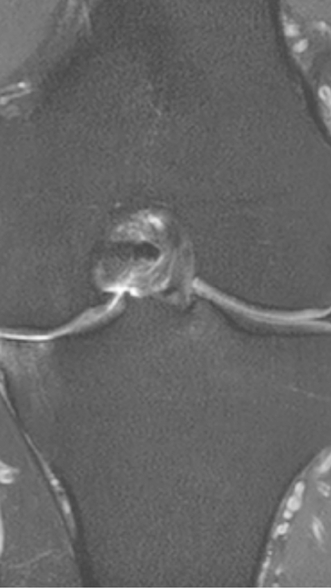

Рецидивирующий синовит коленного сустава

Излечение за 1 процедуру ФДТ Ревиксан

Рецидивирующий бурсит коленного сустава

Излечение за 2 процедуры ФДТ Ревиксан